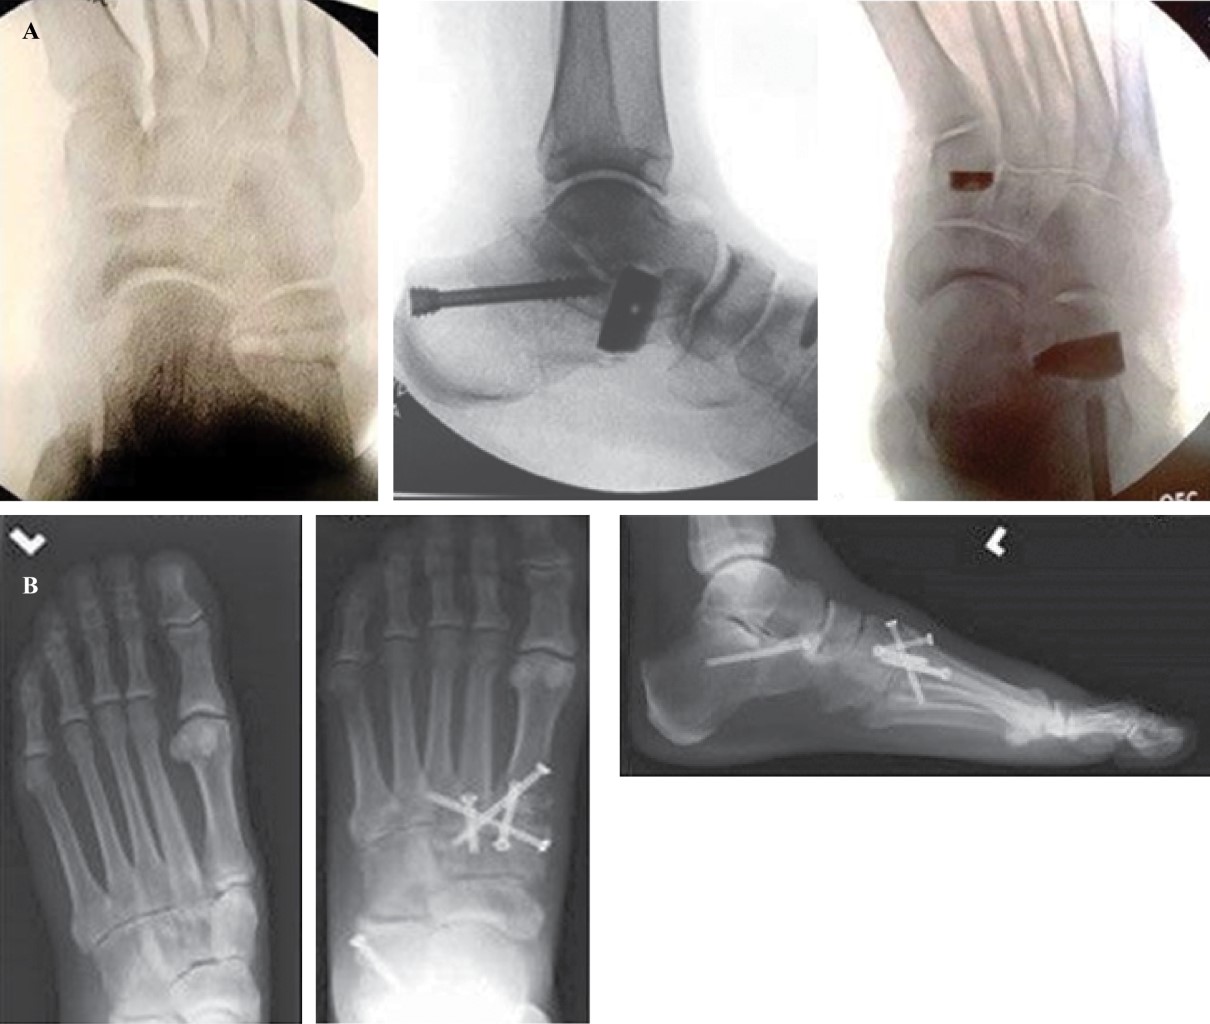

Figure 3